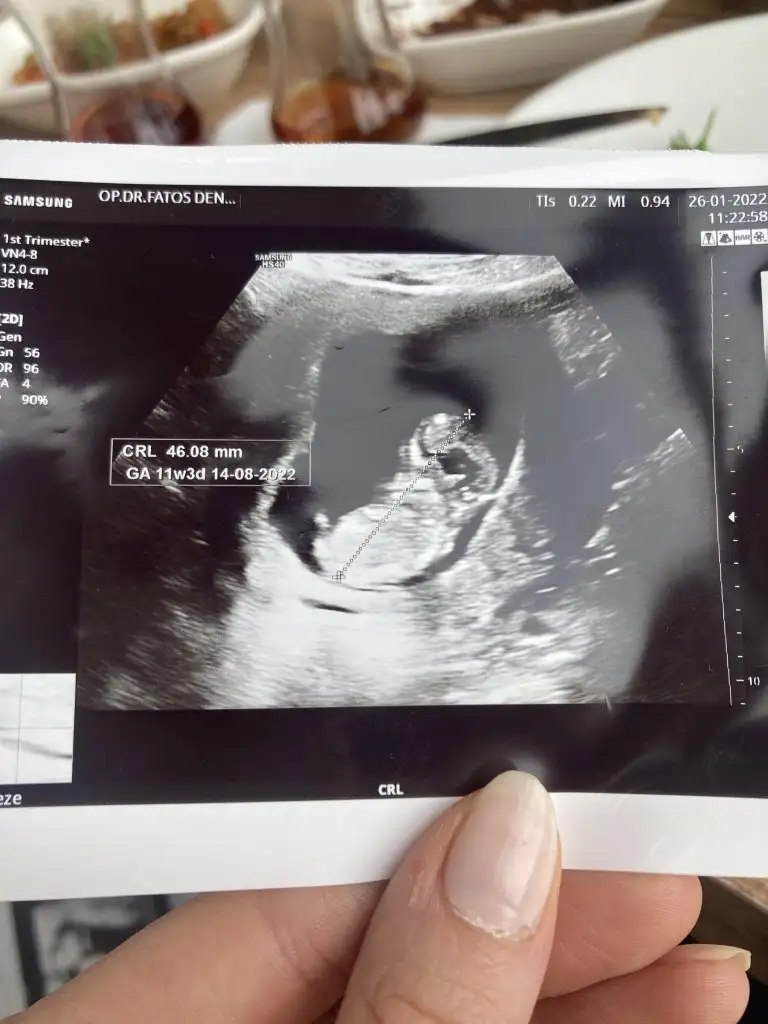

dr soylemeden siz gorun genital nub teorisi ( bebegin cinsiyeti)

11+3 ultrasona gore tahmin eder misin ?